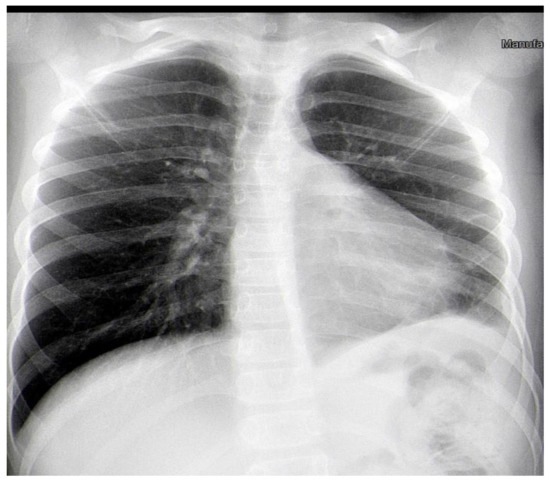

After two weeks, the child was admitted again to the Department of Pediatric Thoracic Surgery. Blood and biochemical tests were in the normal range (leucocytes 8.9 G/L, hemoglobin 136 g/L, hematocrit 0.42 L/L, thrombocytes 281 G/L, CRP 0.06 mg/dL, ASAT 26 U/L, ALAT 17 U/L, creatinine 57 µmol/L). A frontal chest X-ray revealed the persistence of the radiological findings from the last stay (Figure 3). A CT scan showed a zone of consolidation and a typical view of a lung abscess in the left posterior basal segment (Figure 4A,B). Then, the decision for surgery was taken. A left-sided VATS was performed. An abscess (3 cm/4 cm/5 cm) was found in the 10th segment, and an atypical lung resection was performed. After the procedure, the lung specimen was cut, and a foreign body (an awn from the species Hordeum murinum) was found (Figure 5A,B). A 20 Ch drain tube was inserted into the pleural cavity. After the surgery, the improvement was marked. Perioperative and postoperative therapy comprised Sultamicillin, Cefoperazon/Sulbactam, Clindamycin, and postoperative analgesia. The postoperative period was uneventful. The patient was discharged on the 9th postoperative day.

Figure 3. Frontal chest X-ray one day before the surgery.